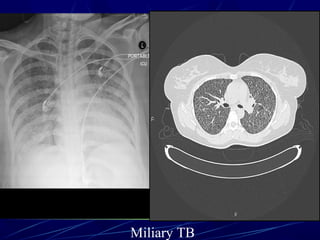

Small random nodules are

seen in:

๏ฌ Hematogenous metastases

๏ฌ Miliary tuberculosis

๏ฌ Miliary fungal infections

๏ฌ Sarcoidosis may mimic this

pattern, when very extensive

Miliary TB